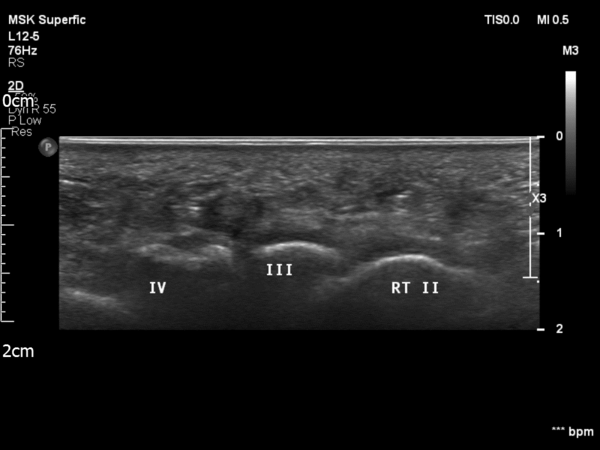

УЗИ нейромы Мортона между 3-й и 4-й головками плюсневых костей

Диагностическое ультразвуковое исследование позволяет динамически обследовать патологии стопы и лодыжки. Это неинвазивный, экономичный и доступный инструмент, который рекомендуется в качестве первой линии диагностики для исключения надрывов связок, тендинита, теносиновита, подошвенного апоневроза, мягкотканных образований или нейромы Мортона. [6] [7]

Диагностическое ультразвуковое исследование оказалось эффективным инструментом для диагностики следующих травм стопы и лодыжки: